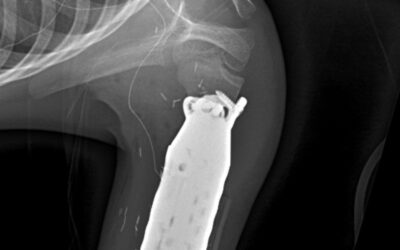

- Patient Profile & Diagnosis: A 10 month old girl presented with a rare and aggressive Ewing sarcoma involving the complete radius bone.

- Treatment Path: After undergoing neoadjuvant chemotherapy, the patient achieved a near-complete radiologic and pathological response—enabling a function-saving surgical plan.

- Innovative Surgical Technique: Dr. Wittig performed a radical resection of the radius, followed by centralization of the carpus directly onto the ulna, creating a stable and functional upper extremity with preserved hand function and natural appearance.

- Outcomes: Three years post-surgery, the patient shows no signs of recurrence. The limb remains stable and cosmetically appealing, with excellent functionality—highlighting the procedure’s long-term success and impact.